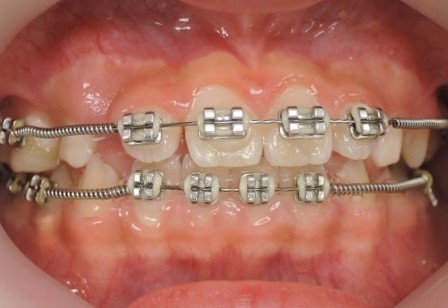

まずは矯正装置(ブラケット)をつけて歯並びを整えていきます。

この開咬状態の原因であるポステリアディスクレパンシィを上図左側にある

MEAW(マルチループ)によって改善していきます。

すると開咬が改善して抜歯(第一小臼歯)することなく正常な咬合状態になります。

治療期間は2年4カ月で終了しました。

はじめに目立たないブラケット(歯に付ける矯正装置)を利用して上顎から歯並びを改善します。その折に同時にレジンを利用する事で咬み合わせの高さも挙上していきます。

歯並びを改善すると受け口がひどく見える時もありますが心配ありません。

次にMEAW(マルチループ)を利用する事で咬み合わせの高さや咬み合う平面の角度を変える事で歯(第一小臼歯)を抜く事無く受け口(下顎前突)を改善していきます。

また、MEAW(マルチループ)はゴムを24時間使用する事で最大の効果を発揮することが出来ます。